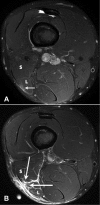

Background: Injury to the distal musculotendinous T junction (DMTJ) of the biceps femoris is a distinct clinical entity that behaves differently from other hamstring injuries due to its complex, multicomponent anatomy and dual innervation. Injury in this region demonstrates a particularly high rate of recurrence, even with prolonged rehabilitation times.

Methods: Acute injury to the DMTJ of the biceps femoris was identified in 106 MRI examinations from 55 patients at a single institution. Each injury was classified as involving the long head, the short head, or both components of the DMTJ, with each component individually graded. Injuries were classified as recurrent if there was a previous MRI demonstrating an acute injury to the DMTJ or if there was scarring present at the site of an acute injury.

Results: Of the 106 acute injuries to the DMTJ of the biceps femoris, isolated injury to the long head component was the most common (51%), with both components involved in [round 42.5% to 43%] of cases. Isolated injury to the short head component accounted for 7% of cases. The recurrence rate for reinjury to the DMTJ was 54% in this series. The date of prior injury was known in 45 of 57 recurrent cases, with 34 of these reoccurring within 3 months (76%) and 40 reoccurring within 12 months (89%). The recurrent injury was of a higher grade than the prior injury in 22 of 44 instances (50%), the same grade in 16 instances (36%), and a lower grade in 6 instances (14%). Thus, 86% of recurrent injuries were of the same or higher grade than prior injury.

Conclusion: These results suggest that high-risk muscle injuries, such as that to the DMTJ of the biceps femoris, should be evaluated using MRI to determine the structural components involved and to assess the extent and severity of injury.